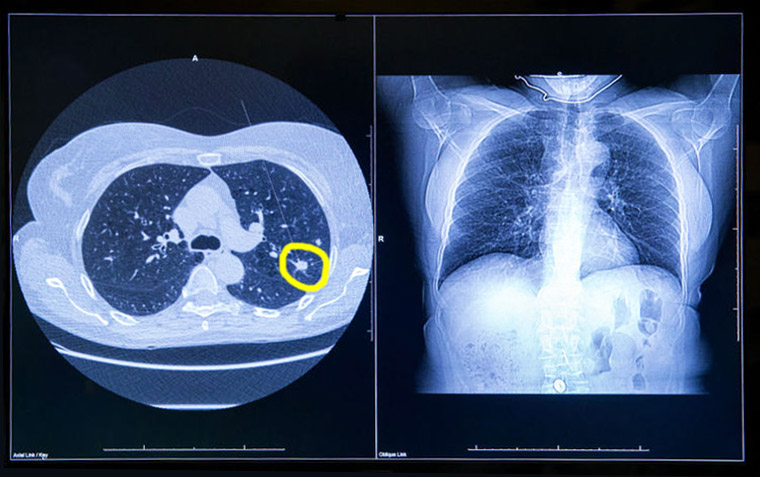

En el estudio danés de tomografía computada de baja dosis para el cribado de cáncer de pulmón se halló que 2 de cada 3 casos detectados podrían corrresponder a sobrediagnóstico. JAMA Internal Medicine, 13 de agosto de 2018